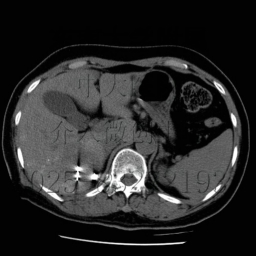

在B超或CT引導下,有目的性地肝穿刺,可開展肝膿腫穿刺排膿、注射藥物,無水酒精瘤內注射治療肝癌等。在進行穿刺取材、診斷的同時,還可以開展診斷性治療,做到診斷治療兩不誤。